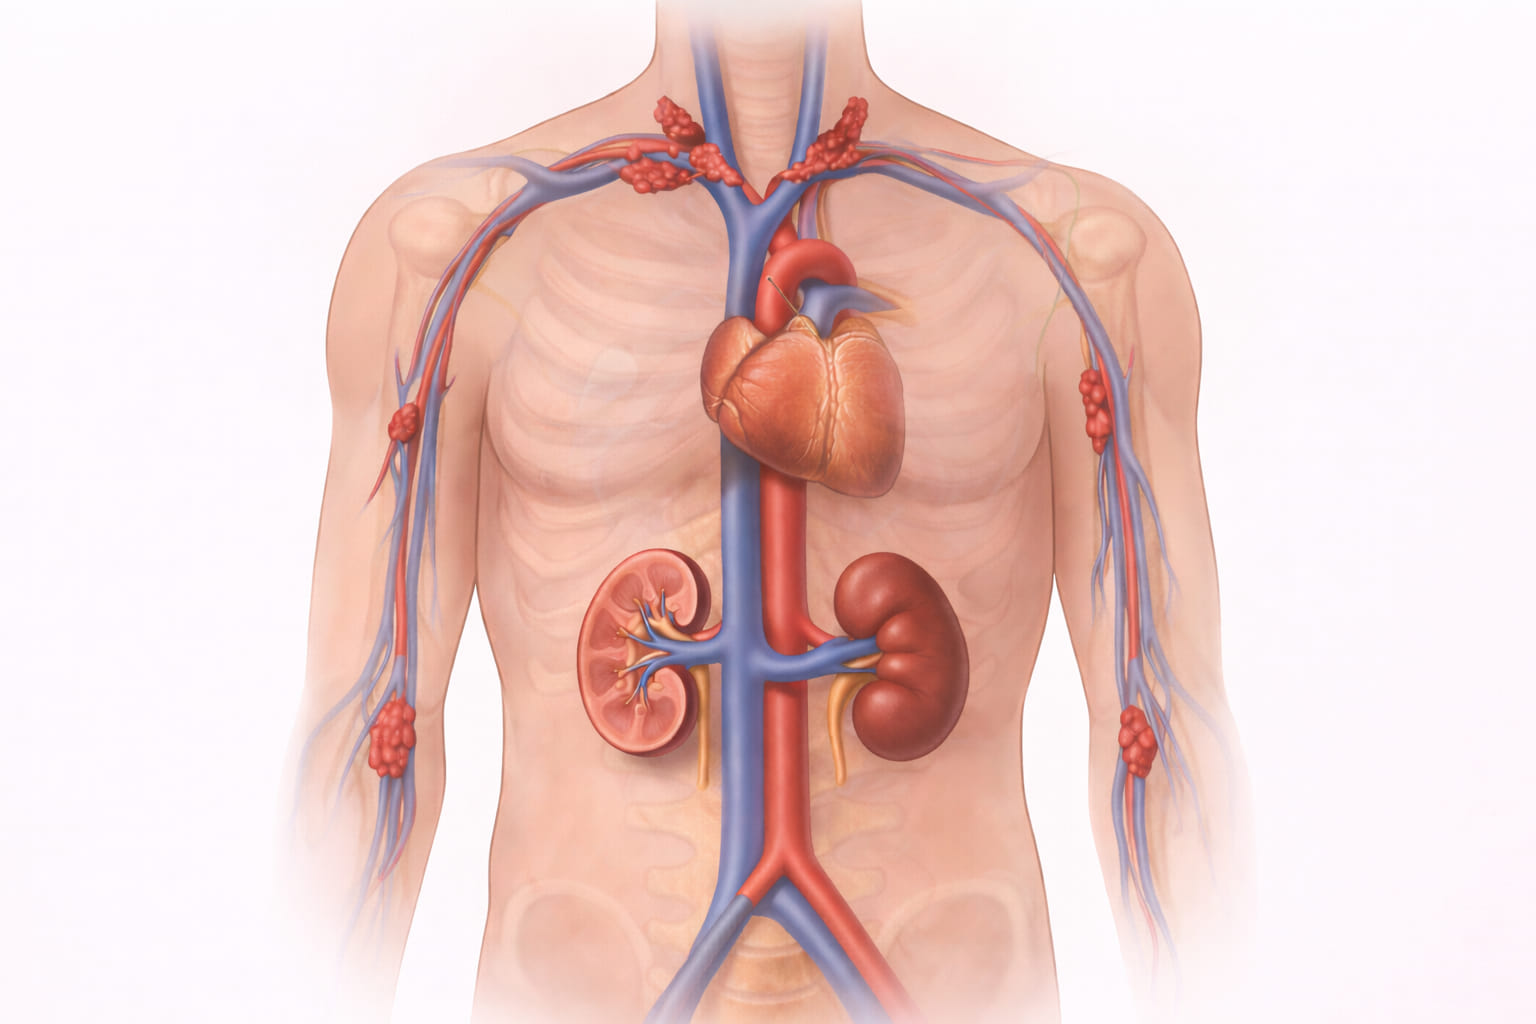

- For patients who depend on long-term dialysis or intravenous therapy, reliable central venous access isn’t optional—it’s life-sustaining. But repeated catheter use can close off the usual veins in the neck and chest, leaving patients with limited options.

A Translumbar Venous Catheter provides a critical solution when traditional access points are exhausted. Instead of the neck or chest, a specialized catheter is placed directly into the Inferior Vena Cava (IVC) through the lower back, giving immediate, high-flow access for dialysis or essential infusions.

- Exhausted Access: Patients who have no usable veins left in the upper body (neck, chest, or arms) due to multiple previous blockages.

- High Flow Rates: The IVC is a large vessel, allowing for the high blood-flow rates required for efficient dialysis.